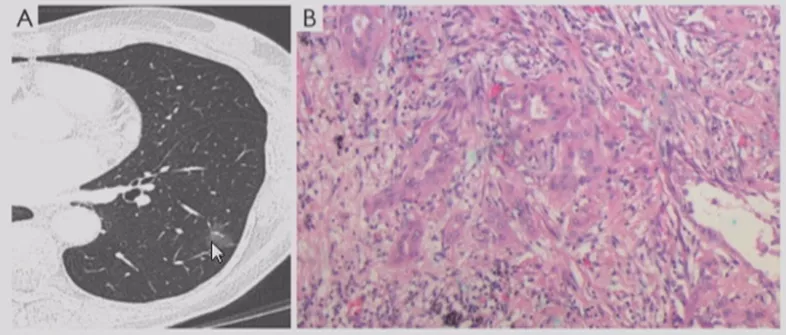

浸润性腺癌(IA)

病灶较前几种类型更大,多为实性或以实性成分为主(>5mm,GGO比例<50%)的结节,形状多为不规则,边界较清楚,开始出现一些明显的肿瘤征象,可有分叶、毛刺、棘突、空泡征、支气管充气征、血管集束征、胸膜牵拉征等。临床医生判断这些征象没有什么问题,但是这个时候对于呼吸医生来说,应该在这之前给病人一个比较合理的判断。